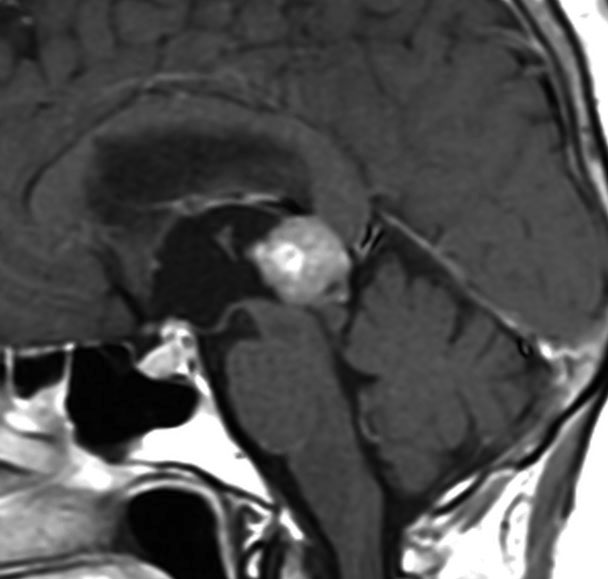

14歳の男の子です。このMRI画像はどう見ても松果体奇形腫 mature or immature teratoma 以外には考えられません。左の写真で脂肪腫が混じっていることが解ります。AFP 130 ng/ml, HCG-beta 30 mIUでしたから,ICE化学療法と放射線治療 (全脳室 25.2グレイ/15分割と局所28.8グレイ,1回線量1.8グレイ)をして少し小さくして(右の写真)から開頭手術しました。全摘出して病理診断は成熟奇形腫でしたが,治療前にはおそらくもっと未熟な部分が混じっていたと考えられます。